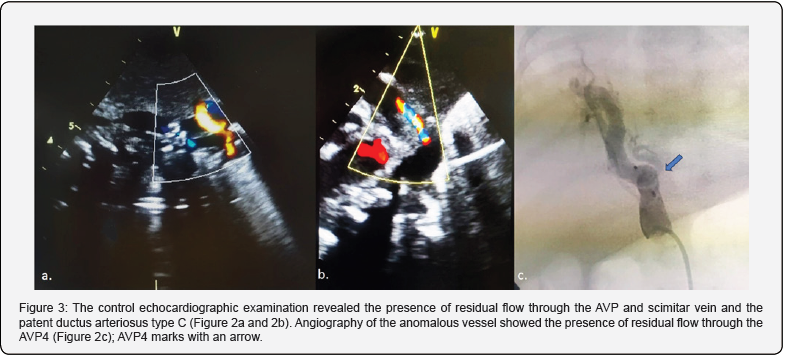

A week after the procedure, the control echocardiography revealed an increased pulmonary blood pressure (peak pressure gradient at the patent ductus arteriosus was 17 mmHg). Residual flow through the AVP and scimitar vein (laminar venous flow) was registered. The PDA type C was 7 mm long, and the pulmonary and aortic ends were 2.8 and 3.5 mm in diameter, respectively (Figure 3 a, b). The PDA and the anomalous artery were closed percutaneously in the second procedure. The procedure was performed with a 4-French sheath and catheters through the right femoral artery. Angiography of the anomalous vessel showed the presence of residual flow through the AVP (Figure 3c), whereas aortography showed that the narrowest diameter of the PDA was 2 mm. The detachable Cook Coil 5x5 was positioned below the AVP and released, resulting in complete vessel occlusion, confirmed on control angiography after 5 minutes. On the other hand, a thinner collateral vessel was observed below the devices (Figure 4a). The second, more delicate supply collateral vessel was occluded with the detachable Flipper Coil 3x3 without residual flow (Figure 4b). The detachable Flipper coil 3x5 was appropriately positioned and released in the PDA. Complete vessel occlusion was executed at the end of the procedure (Figure 4c).